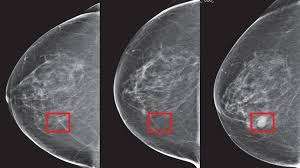

AI தொழில்நுட்பம் மூலம் மார்பக புற்றுநோயை 5 ஆண்டுக்கு முன்பே கண்டறிய முடியும் என்று அமெரிக்க நிறுவன ஆய்வறிக்கையில் தெரியவந்துள்ளது.

அமெரிக்காவின் மாசாசூசெட்ஸ் பல்கலைக்கழகம் (Massachusetts Institute) மற்றும் ஜமீல் கிளினிக் (Jameel Clinic) ஆகியவை இணைந்து மார்பக புற்றுநோயை கண்டறியும் செயற்கை நுண்ணறிவு (AI) தொழில்நுட்பத்தை கண்டுபிடித்துள்ளனர். இதற்கு மிராய் (Mirai) என்று பெயரும் வைத்துள்ளனர்.

இந்த தொழில்நுட்பம் மூலம் 5 ஆண்டுகளுக்கு முன்பாகவே மார்பக புற்றுநோயை கண்டறிய முடியும்.

இந்த அறிக்கையில், "அமெரிக்காவில் 8 பெண்களில் ஒருவருக்கு மார்பக புற்றுநோய் ஏற்படுகிறது. இதனை மேமோகிராம் மூலம் கண்டறிய முடியும் என்றாலும், சில நேரங்களில் மருத்துவர்களால் முன்கூட்டியே கண்டறிய முடியவில்லை.

இதனை முன்கூட்டியே கண்டறியும் வகையில் ‘மிராய்' என்ற பெயரில்புதிய செயற்கை நுண்ணறிவு தொழில்நுட்பம் கண்டுபிடிக்கப்பட்டுள்ளது.

இதனை பயன்படுத்தி 5 ஆண்டுகளுக்கு முன்பாகவே மார்பக புற்றுநோயை கண்டறியலாம். இதனால் ஆரம்ப நிலையிலேயே சிகிச்சை அளிக்க முடியும்" என்று கூறப்பட்டுள்ளது.